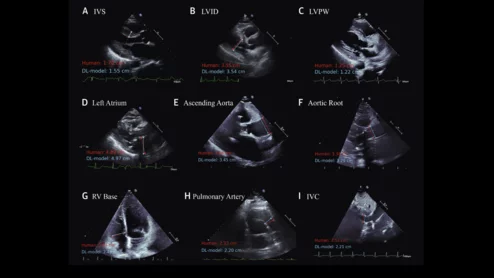

Cardiologists have developed an open-source artificial intelligence (AI) model capable of accurately evaluating a long list of measurements on echocardiography results. The group detailed the development and validation of that model in the Journal of the American College of Cardiology. A comparison of measurements made by a sonographer (in red) and predictions from the deep learning model (in light blue) across 9 echocardiographic parameters. Image and caption courtesy of Ouyang et al., JACC.

The algorithm, trained on more than 150,000 TTE studies, can calculate 18 different measurements regularly used in echocardiography